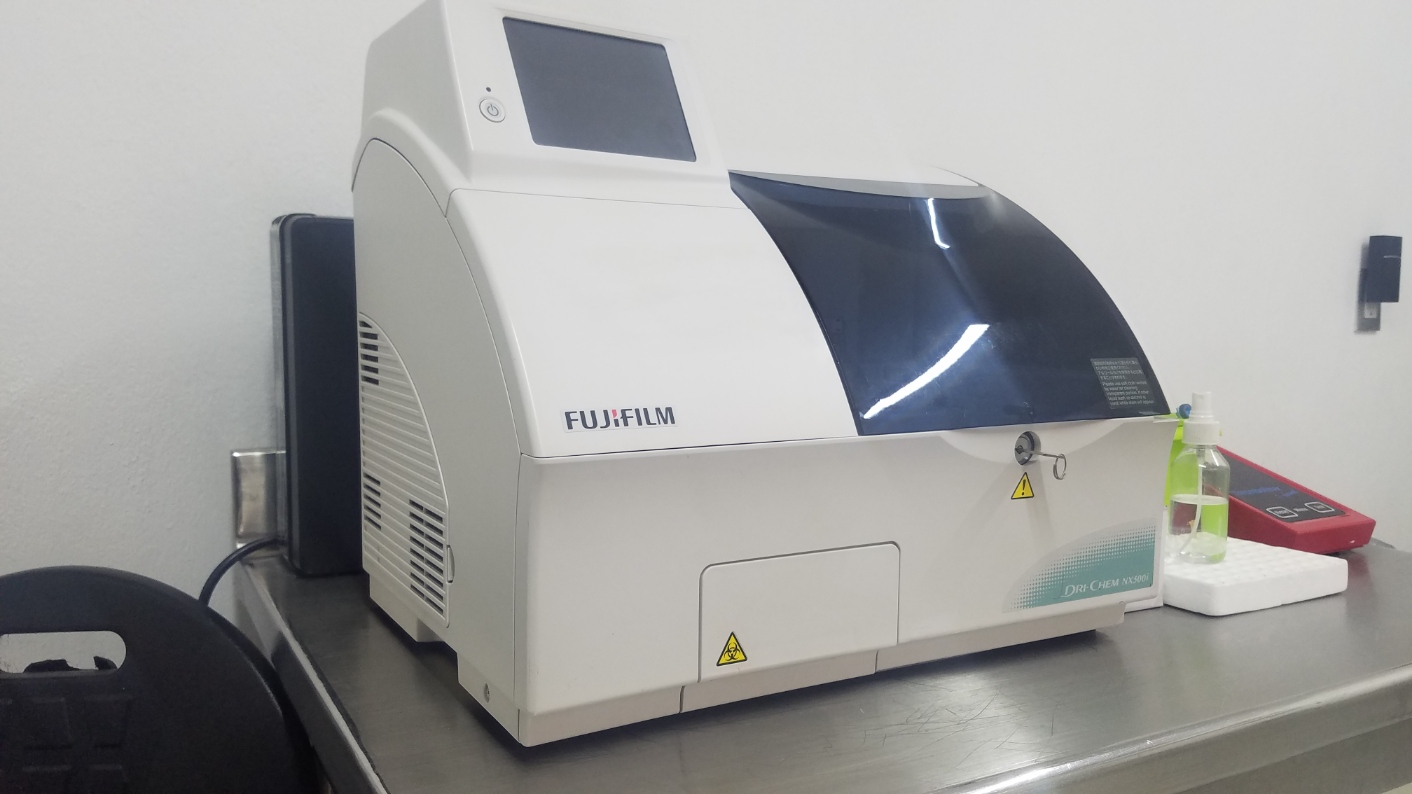

En Biosoma somos profesionales, contamos con mas de 10 años al servicio dando los mejores resultados a nuestros clientes.

Las pruebas de sangre se usan para medir o analizar células, sustancias químicas, proteínas y otros componentes de la sangre. Son uno de los tipos más comunes de pruebas de laboratorio.